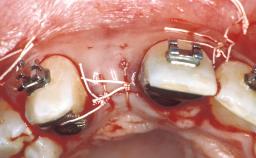

The 23-old-male patient, a light smoker (less than five cigarettes per day), presented with a non-vital and discolored tooth 21. The patient was in good general health, and his medical history was without significant findings. He suffered from pain originating from mobile tooth 21. Because of the discoloration of tooth 21, the patient asked to have his esthetic appearance improved.Tooth 21 had been endodontically treated after trauma,and an apicoectomy had been performed. At full smile, the patient had a medium smile line, exposing the full teeth and part of the gingiva. The patient’s gingival biotype was medium thick, with a sufficiently thick band of attached keratinized gingiva. The tissue was free of recessions or other defects.